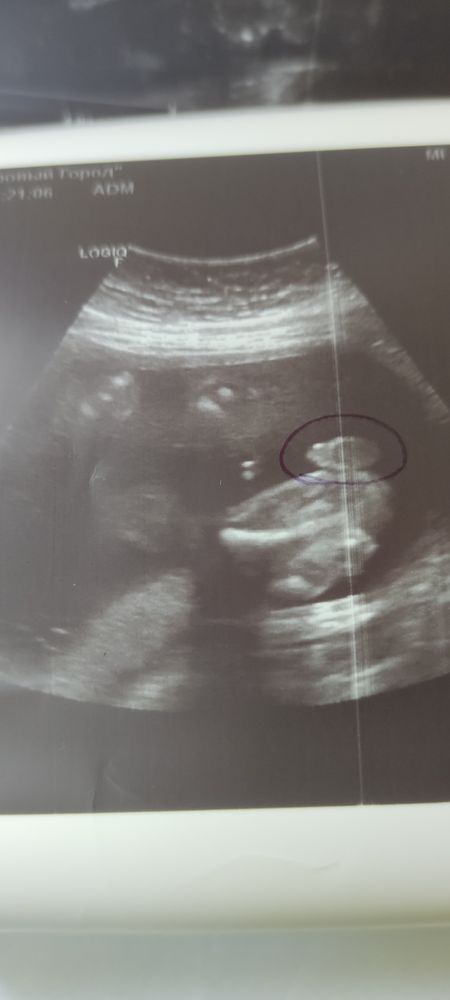

Изображение Даже обвели😁 а то у нас отец сомневался до последнего 🤣🤣🤣 Елизавета,

09.10.2023

Катя Ульянкина, теперь решил показаться во всей красе😂😂😂😂

Елизавета, Ага🤣🤣🤣

11.10.2023